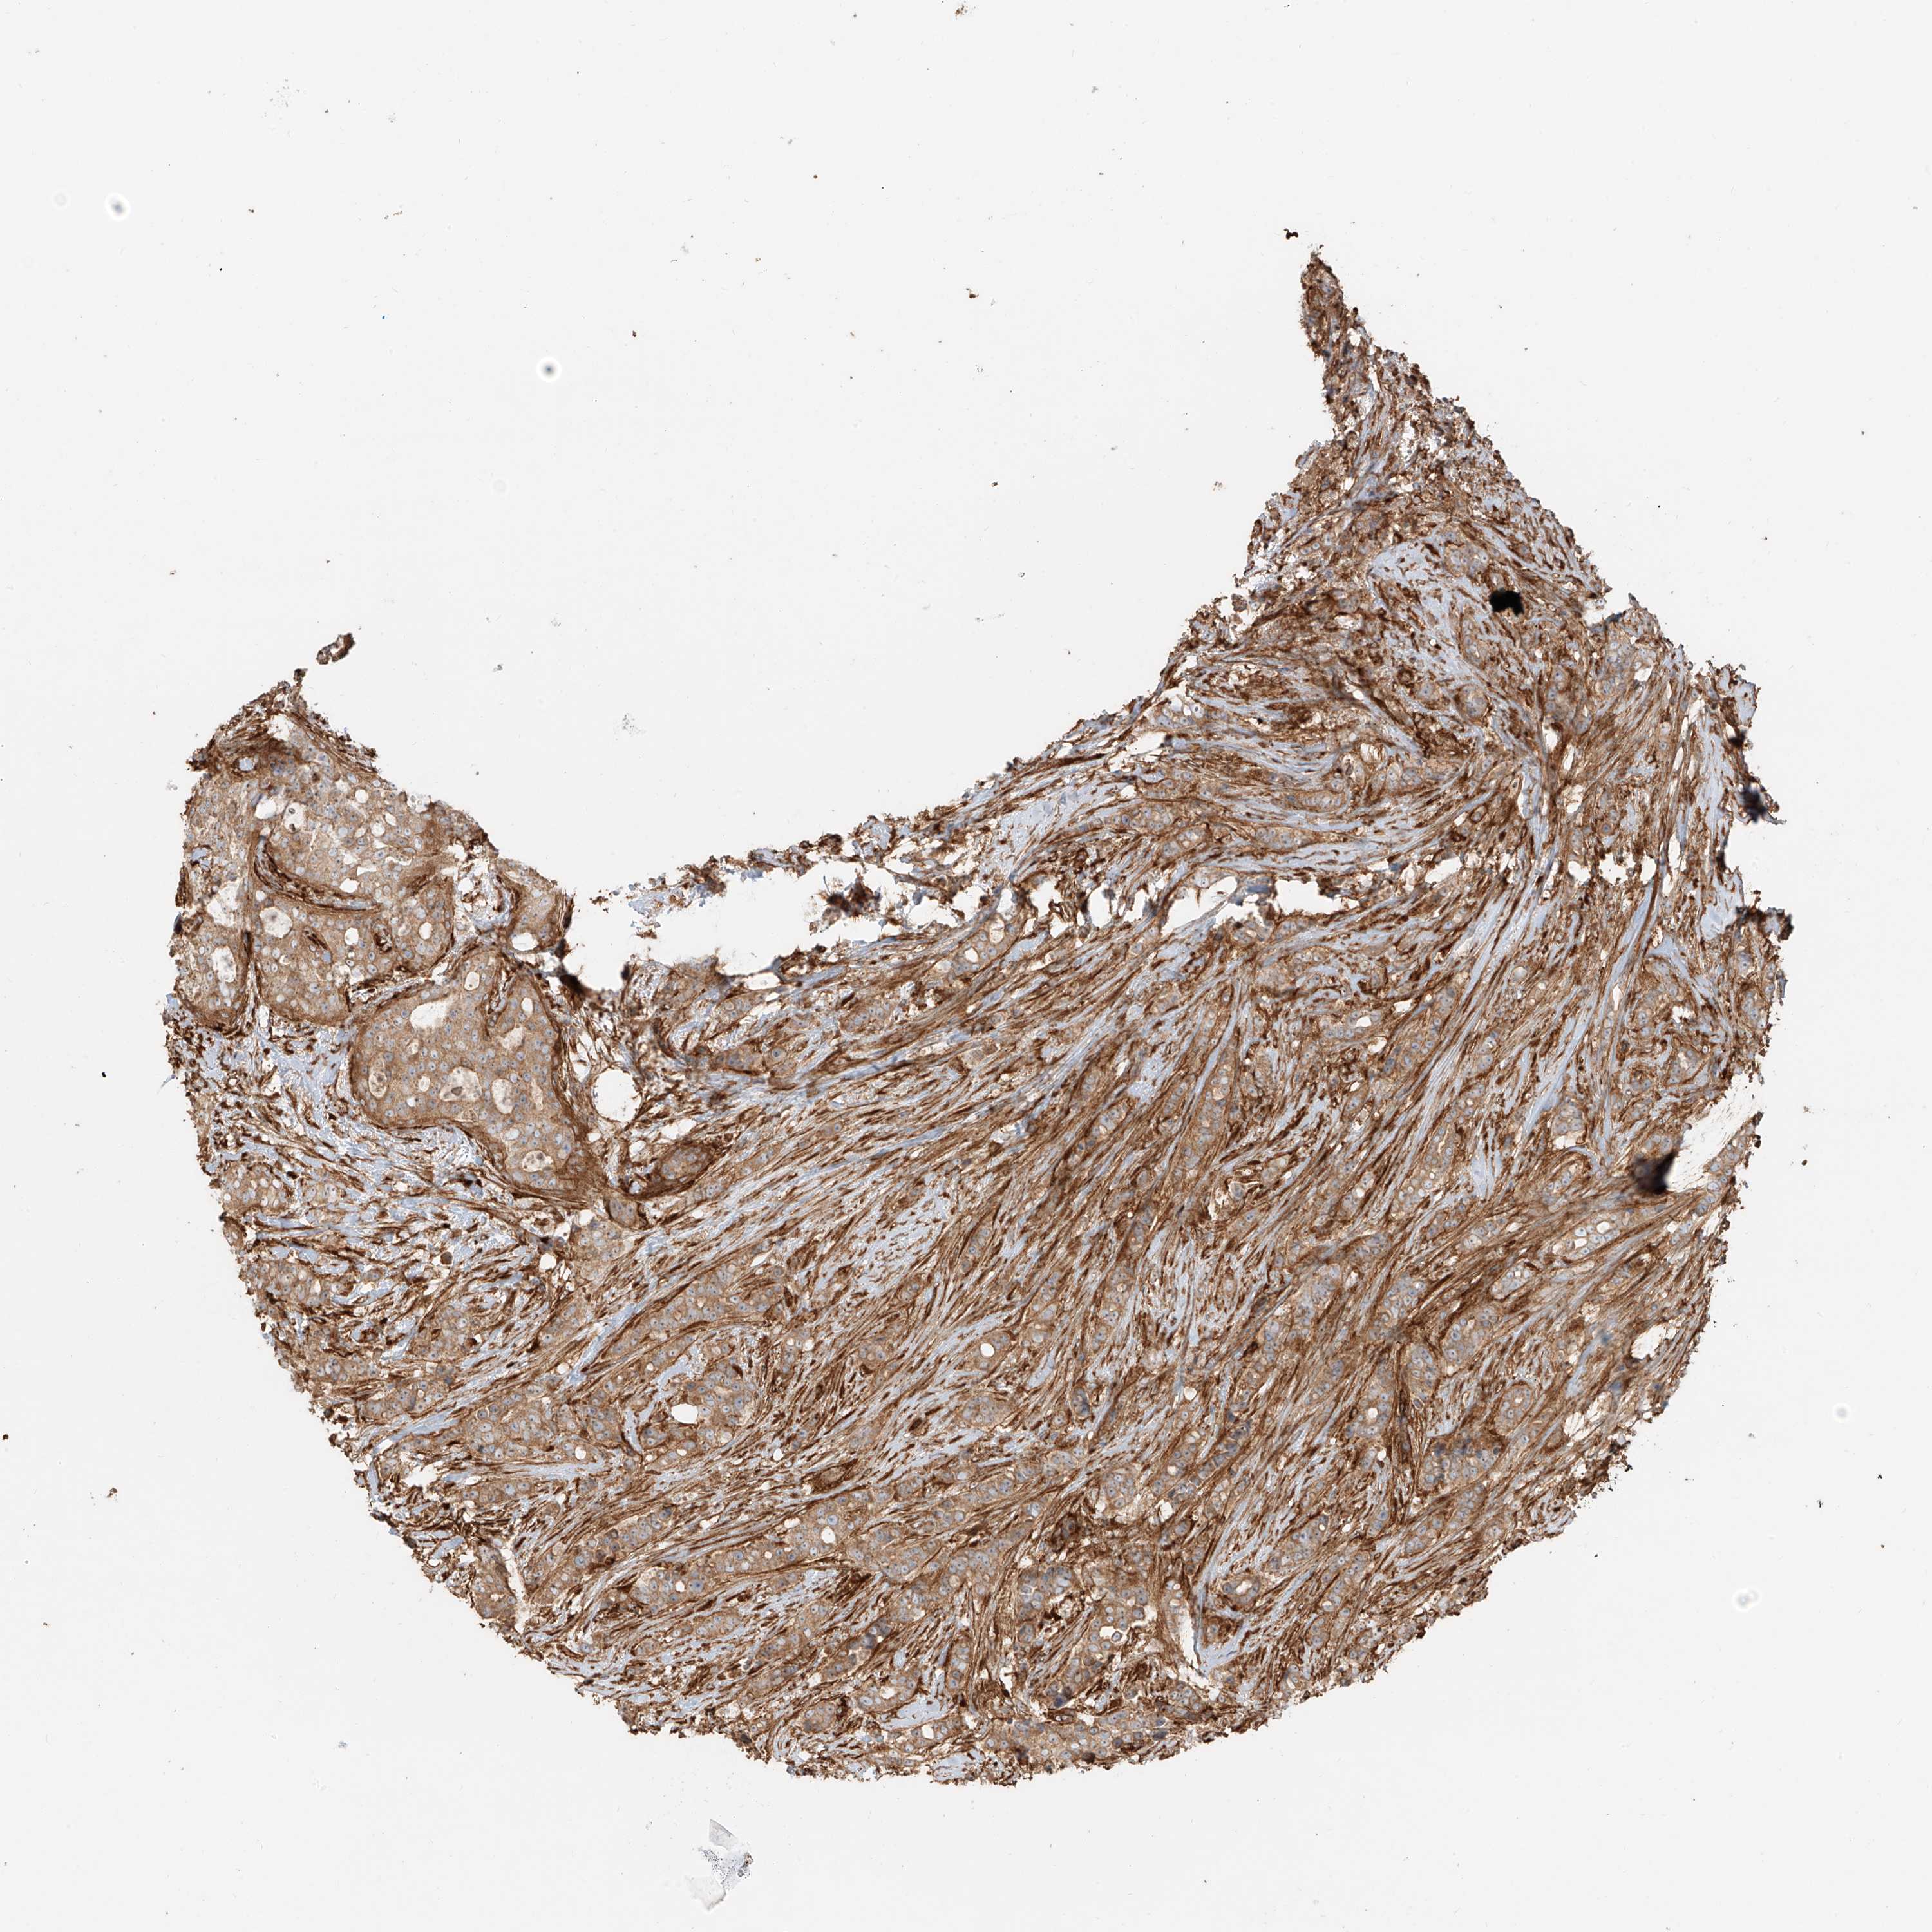

CANCER BREAST CANCER Show tissue menu

BRCA TCGA BRCA VALIDATION PROTEIN EXPRESSION

Breast cancer

Human cancer

Breast invasive carcinoma

SNX9 is potential prognostic, high expression is unfavorable in Breast Invasive Carcinoma (TCGA)